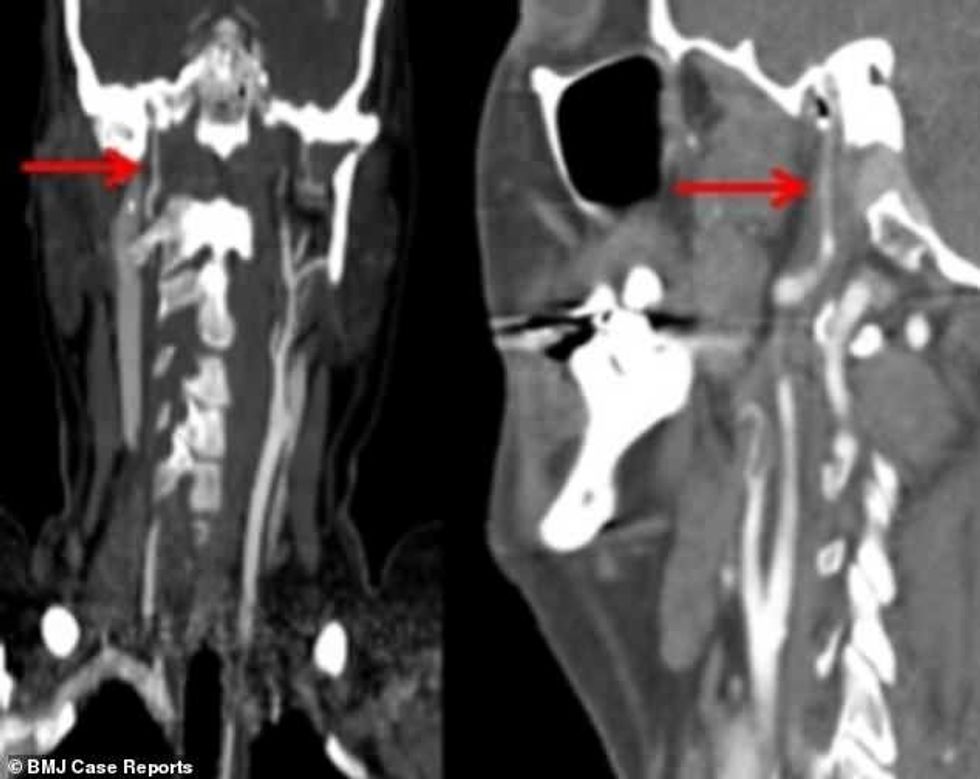

Vizitën e parë e bëri pas dy javësh, kur kapakët e syve po i mbylleshin vet, ndërsa njerëzit i shihte në forma dhe madhësi të ndryshme. Fotografimi me rreze X, ka treguar se i është shkëputur arteria që ia furnizon trurin me gjak dhe oksigjen.